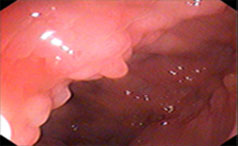

慢性胃炎应该要如何预防?慢性胃炎是常见的消化疾病,这是由于很多原因所造成的。慢性胃炎预防是很重要的,因为患了慢......【详情】

常见症状:恶心呕吐、食欲减退

餐后饱胀、反酸嗳气

【导语】急性胃炎是怎么引起的?嫩江江洲胃肠专科医院【咨询预约电话:1......【详情】